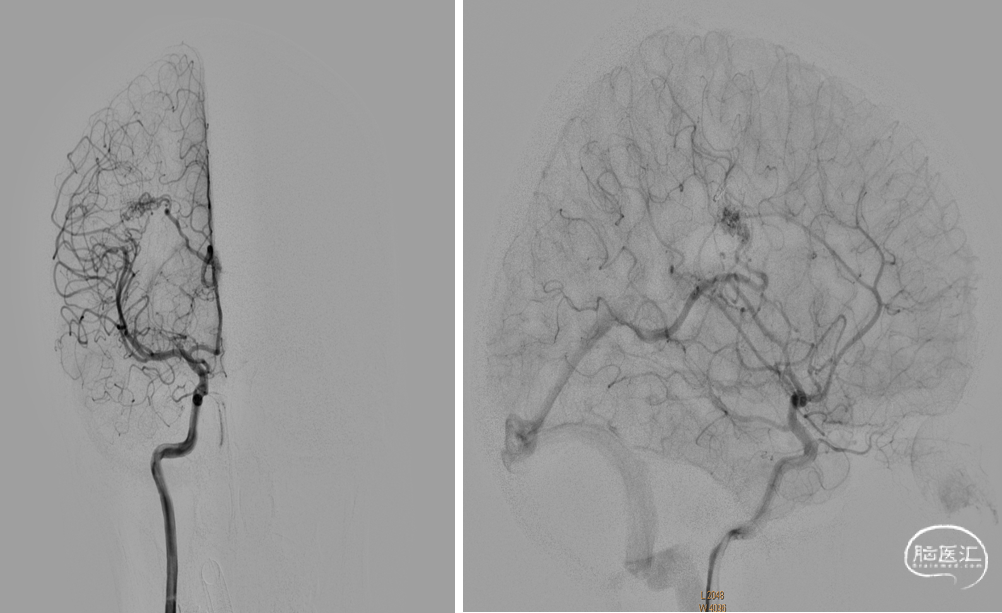

CBCT:无出血,术后无明显不适

术后4个月复查DSA血管畸形无复发